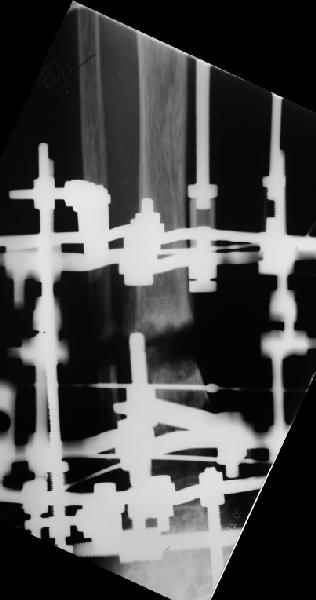

Аппарат - чтобы плавно исправить ось. В приложении - снимки на момент окончания коррекции в аппарате, фото с операции, и послеоперационная рентгенограмма.

Диаметр гвоздика 10,5 мм. Пришлось укорачивать до 23 см - уж очень миниатюрная дама, отверстия насверлил под 45 градусов, под 5 мм винты. По оси удалось сблизить до этого положения. Заперли гвоздь пока статически с планом через 2 месяца верхний винт убрать. Но это ей придется уже в Ташкенте сделать. Что скажете? Спасибо.

In attachment - x-rays at the end of alignment, the surgery, and result. The nail was cut to 23 cm. Four 45 degree holes were pre-drilled at the distal nail tip. The nail was locked statically

after some impaction. Dynamization is considered in 8 weeks. Any comments/critics?

Отправитель: Alexander Chelnokov 27 Апрель 2005, 02:09

А вдруг там все-таки от дистракции образуется регенерат, хоть дохленький? На созревание и зарезервировали 2 месяца стабилизации.

Если регенерата совсем не будет - после отпирания гвоздя отломки начнут сближаться до полного контакта. А если все-таки будет - еще и ~1 см выиграем.